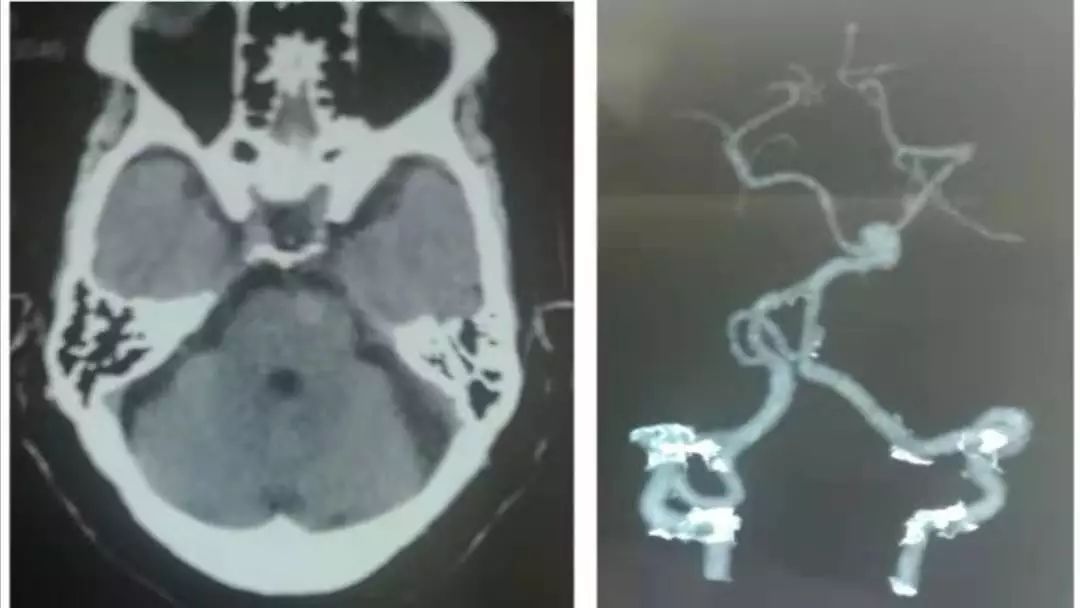

诊断脑栓塞是没有问题的,重点在于栓子来源的筛查。对于病因,群里老师们的总结已经很有一套;对于这个患者,却画风突变,1年后癫痫发作再次入院,颅脑影像如下:

答案:心脏黏液瘤。

近期群内发过一个手术切除后的心脏黏液瘤标本视频,直观生动印象深刻。心脏黏液瘤是最常见的原发性心脏肿瘤,占原发性心脏肿瘤的 50% 以上,70%发生在左心房。心脏黏液瘤具有良性特征,但因其质脆易碎易脱落进入血液循环并转移至全身其他部位,产生不良后果,心脏黏液瘤可具有以下3种心脏外转移的病理学过程:脑血管梗死引起缺血性卒中,实质性肿瘤定植、转移和肿瘤性多发性脑动脉瘤形成、伴或不伴出血。

1894年Marchand首次报道心脏黏液瘤导致多发性颅内动脉瘤形成,它是心脏黏液瘤的中枢神经系统并发症之一。心脏黏液瘤导致多发性颅内动脉瘤形成的可能机制有:(1)血管损伤理论:心脏黏液瘤细胞栓子脱落,经体循环进入脑血管,脑动脉末梢管腔直径小,瘤栓附着于微小动脉壁上,导致血管内皮损伤、瘢痕形成,引起颅内动脉瘤形成;(2)肿瘤定植理论:肿瘤细胞进入脑血管系统后,仍可以保持活力并在局部定植生长。肿瘤组织破坏血管壁,甚至血管壁整个基层均被肿瘤组织破坏、替代,这样可使得其在造影时不仅像真的动脉瘤一样呈瘤样扩张,还有造影剂明显滞留的表现。定植在脑血管内壁的肿瘤细胞有不同的生物学行为,不同的生长速度、方式,既可处于生长休眠状态也可最终坏死,这就可以解释迟发性病变以及多样的动脉瘤形态。在以上两种假说中,脑梗死事件都会发生。而多数学者赞同肿瘤定植理论,有文献报道在组织病理学研究中已经证明了动脉瘤壁中含有活性黏液瘤细胞的增殖及其对内弹力层的侵袭破坏。